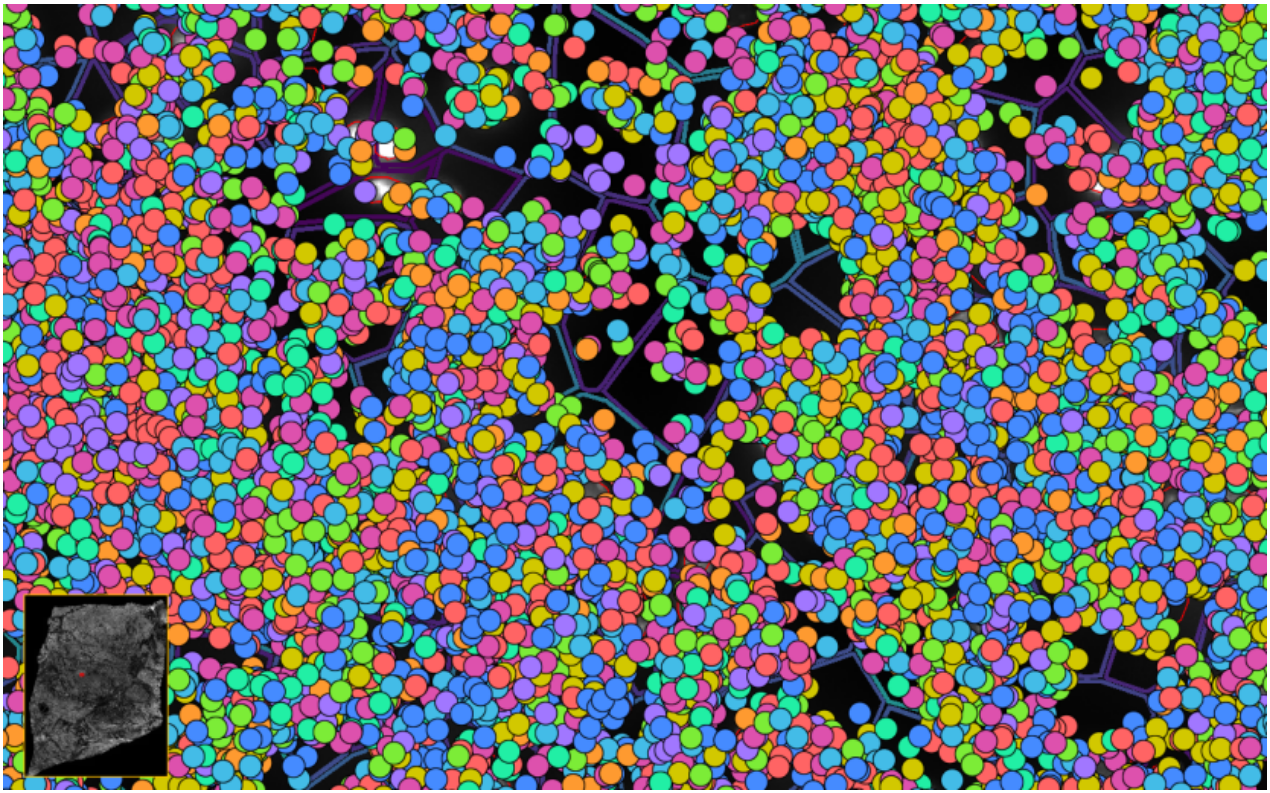

image.png

ͼ4-1£ºÀûÓÃDAPI¶Ôϸ°ûºËȾɫ £¬½áºÏÉî¶È½ø½¨²½Öè´§¶ÈÆëÈ«µÄϸ°ûÌìǵ